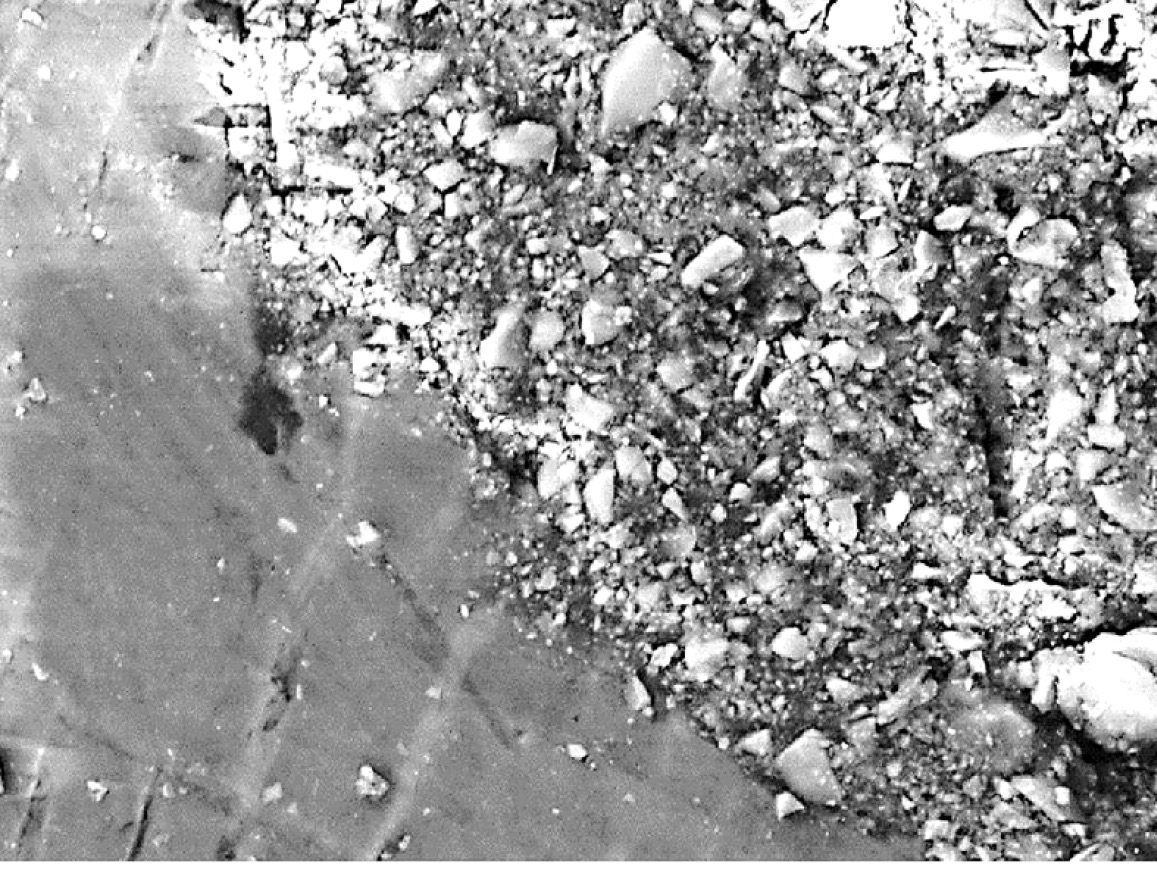

In the first group (Fig. 5), there were small violations of the marginal fit along the entire perimeter of the restoration. On average, out of 10 examined teeth - in 20% of cases.

In the second study group, 60% had violations of the marginal fit of the restoration. On the electron diffraction pattern, at the border of the restoration, inclusions (Fig. 6) from microbrush fibers were observed. We hypothesize that the Prime&Bond Universal adhesive system (Dentsply) affected the fibers and caused them to fall out of the plastic rod.